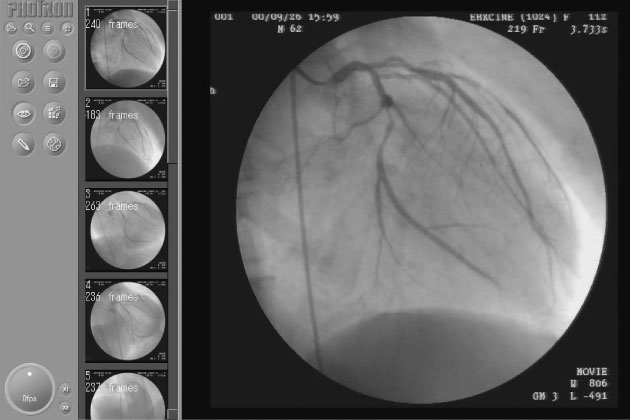

広島市立安佐市民病院様

[多機能化および使用領域拡大の実際]

IVR時における透視像保存の有用性と将来展望 ~Kada-Rec2活用の観点から~ -